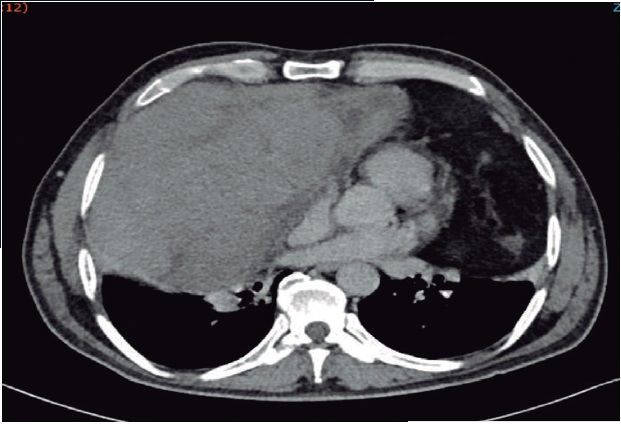

La radiografía y tomografia computarizada, suelen ser suficientes en el abordaje diagnóstico, tanto para dirigir la biopsia percutánea, como para la estrategia quirúrgica. En la radiografía de tórax (Figura 2a) lo usual es observar un ensanchamiento del mediastino o una sombra de alta densidad. La tomografía computarizada puede distinguir un tumor heterogéneo con densidad grasa, márgenes lisos o lobulados bien definidos, con desplazamiento de estructuras vasculares, nerviosas y bronquiales, sin adenopatías, de teratomas, fibromas, y quistes16,17. La presunción diagnóstica de la histología del sarcoma por tomografia computarizada alcanza 60% en centros especializados por las características típicas de la imagen (Figura 2b).

Hombre de 52 años de edad con disnea progresiva en los últimos 2 años. En los últimos meses presentó presión torácica y disfagia para sólidos. a) Radiografía de tórax. Lesión heterogénea con opacidad en los 2 tercios inferiores del tórax bilateral, b) TAC de tórax simple. Ventana mediastinal y pulmonar. En el mediastino anterior y hacia el lado derecho (cabeza de flecha) se identifica tumor sólido con zonas hipodensas en el interior de bordes definidos sin infiltración a otros órganos, el tumor con diámetro mayor de 21 cm con desplazamiento cardiaco a la izquierda. Otra lesión (flecha) heterogénea de 15 cm también en el mediastino anterior, lateralizado a la izquierdo adyacente a la grasa pericárdica, sugerente de liposarcoma.

Figura 2 Características radiológicas del sarcoma de mediastino anterior .